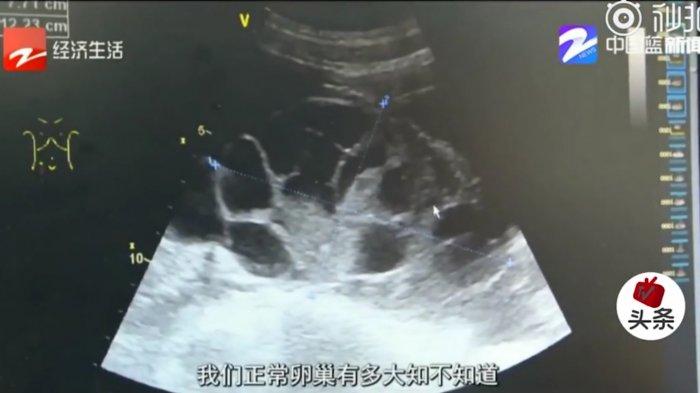

Mahasiswi tersebut didiagnosis menderita Ovarian Hyperstimulation Syndrome yang dapat terjadi ketika ovarioum terlalu terstimulasi untuk pertumbuhan telur dan cairan yang menumpuk di sekitarnya.

Dokter Hu Jinhui dari departemen ginekologi rumah sakit mengatakan, lebih dari lima liter cairan dikeluarkan dari perutnya.

"Indung telurnya telah membesar seolah dia telah hamil selama tujuh atau delapan bulan," kata Dr Hu.